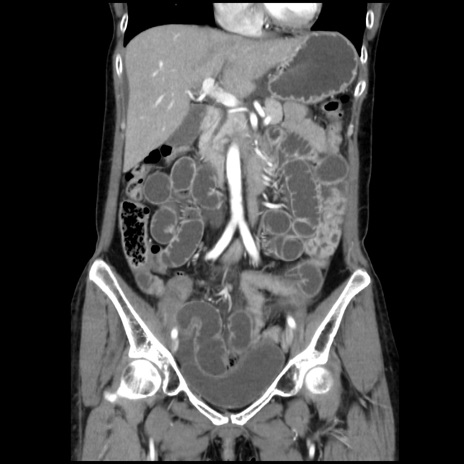

症例32(冠状断像)

【症例】40歳代 女性

【主訴】上腹部痛、嘔気・嘔吐

【現病歴】約9時間前頃から急に上腹部痛、嘔気、嘔吐が出現。改善しないため救急要請。

【既往歴】子宮頚癌(広汎子宮全摘術、放射線療法)、腸閉塞

【身体所見】腹部:平坦、軟、腸雑音亢進、上腹部を中心に腹部全体に圧痛あり。

【データ】WBC 8400、CRP 0.03